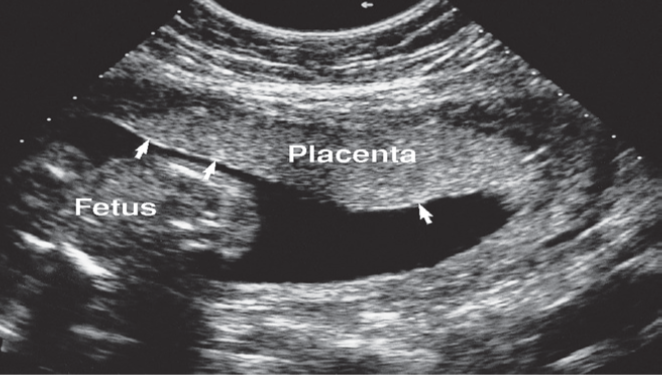

Placental imaging

The placenta is easily evaluated sonographically as well as on MRI.

By the ninth week, it is seen as a well-defined intrauterine structure lining the inner wall of a portion of the uterine cavity.

Abnormalities related to the placenta may be diagnosed on ultrasound, including placental haemorrhage and placenta previa (placenta remains positioned over the lower uterine segment after the 36th week of pregnancy).

Placenta seen on a longitudinal scan at 18 weeks’ gestation. The chorionic plate is seen as a thin line of bright echoes (arrows).